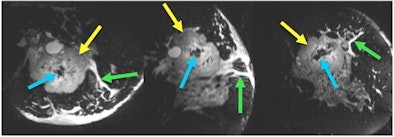

![]() |

| 3D T2-weighted images acquired with the prototype 18-channel breast coil in four minutes from a patient with a locally advanced biopsy-proven invasive ductal carcinoma (yellow arrows). Fine morphological detail, including central low-signal fibrosis (blue arrows) and edema (green arrows), are depicted clearly in axial, sagittal, and coronal planes. Image courtesy of Stanford University. |